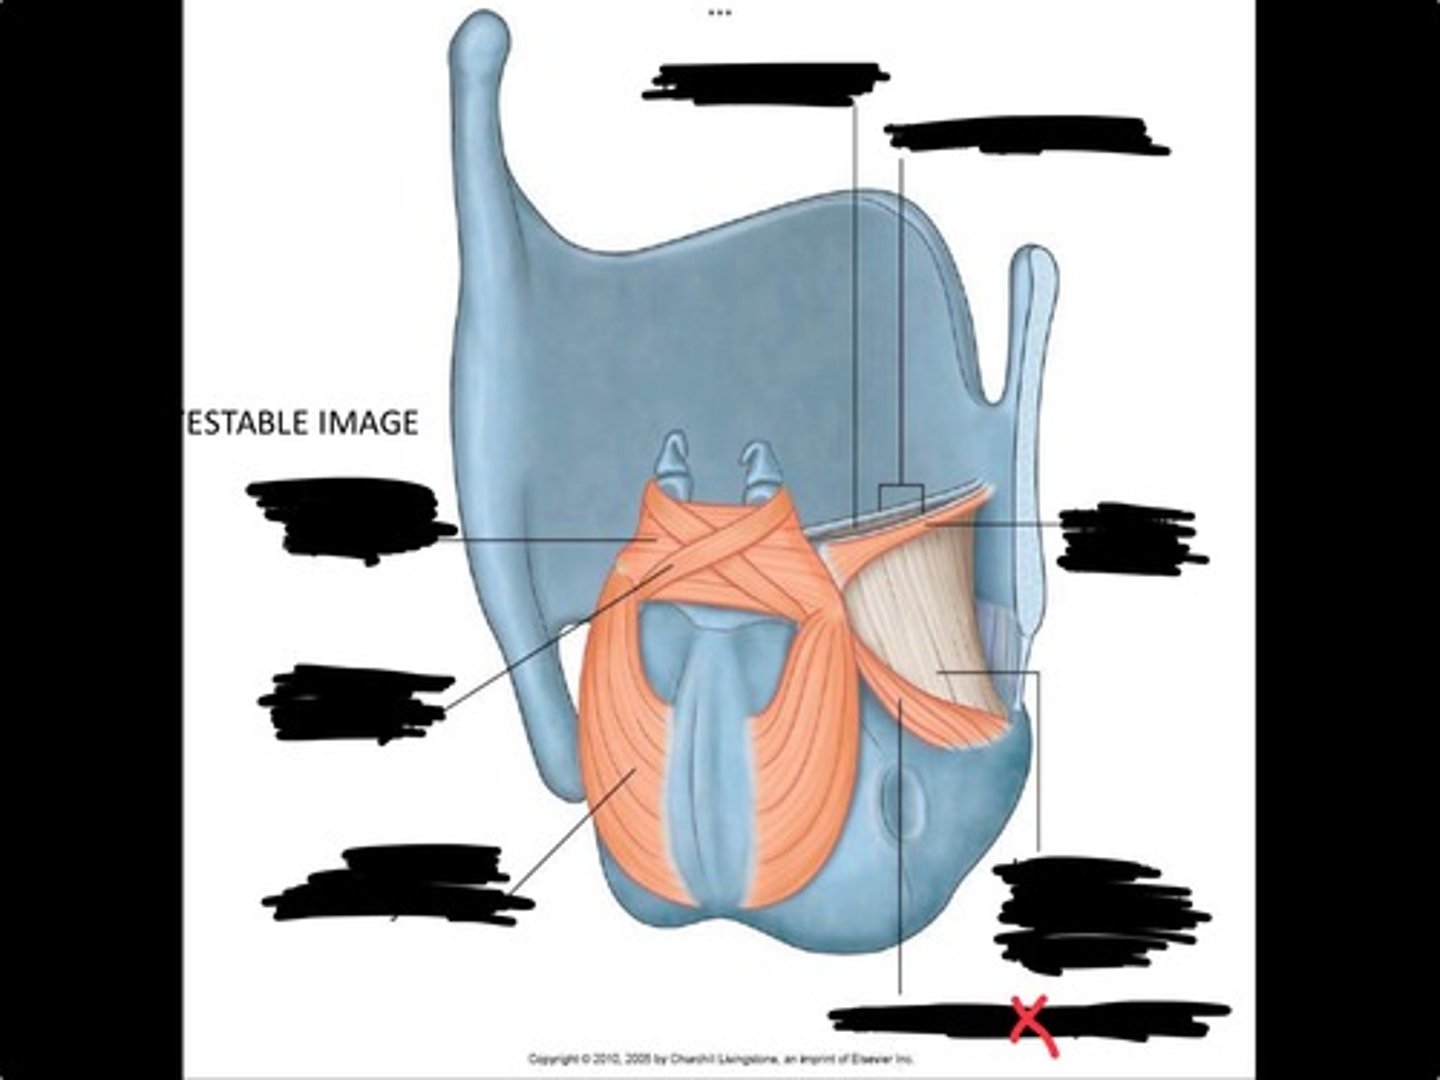

Vocal process of arytenoid

Conus elasticus

Vestibular ligament

Quadrangular membrane

Epiglottis

vocal ligament

Aryepiglottic ligament

Muscular process of arytenoid

Corniculate cartilage

Posterior crico arytenoid

oblique arytenoid

transverse artyenoid

Rima glottidis

Vocal ligament

Vocalis muscle

Lateral cricothyroid ligament

Lateral cricoartenoid